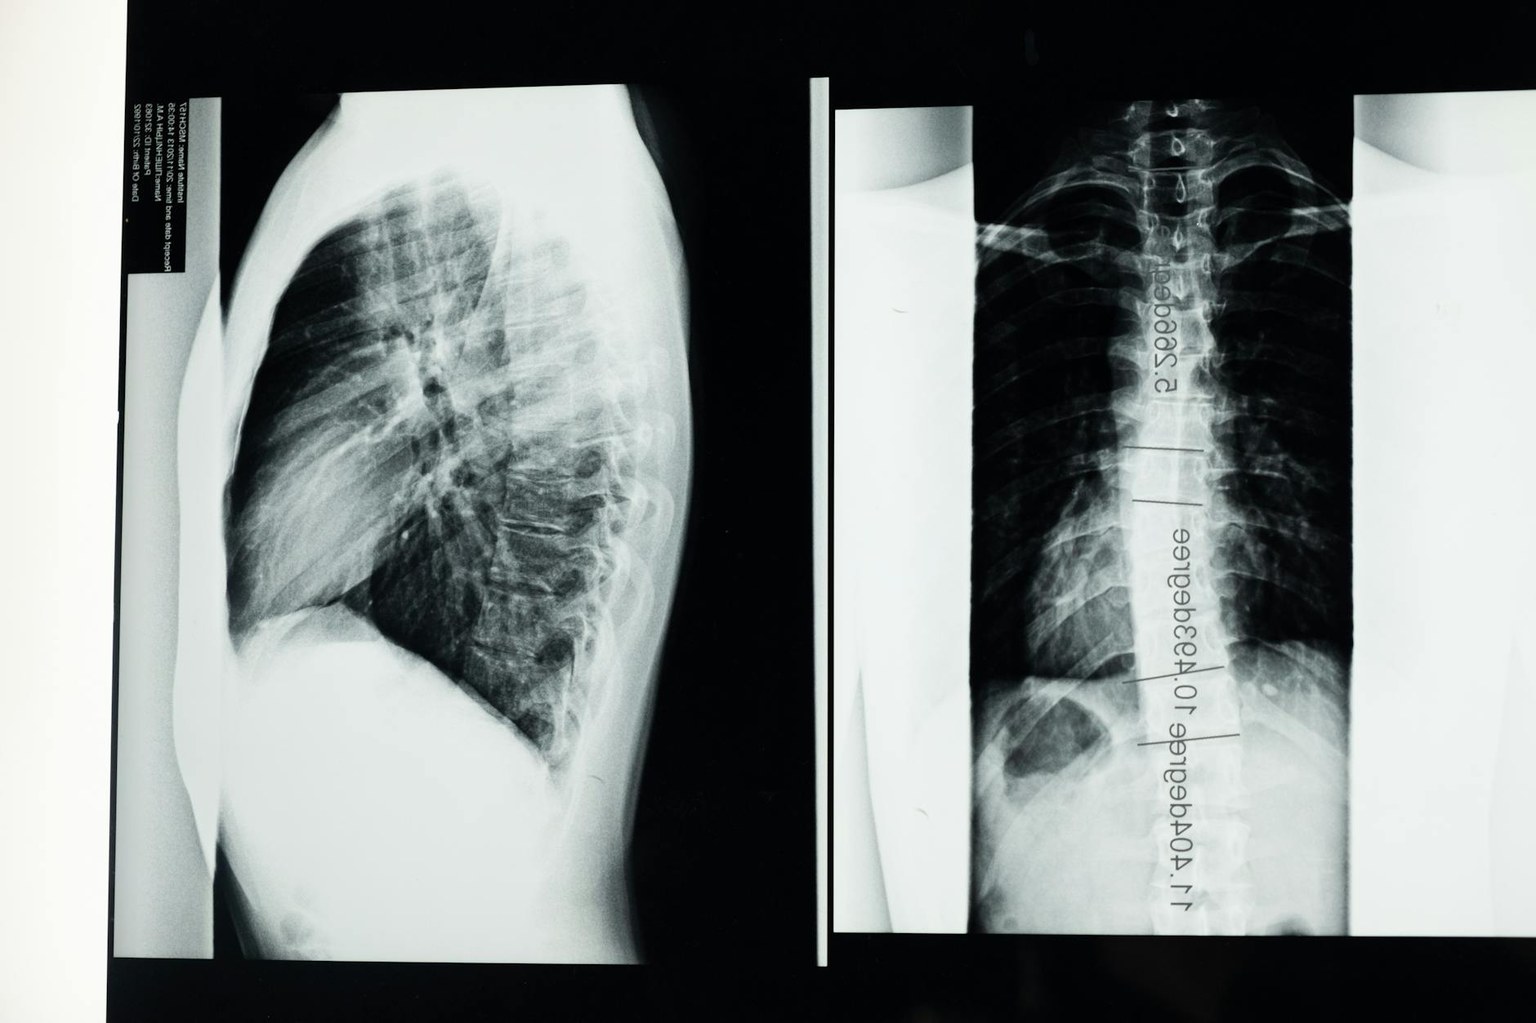

- при одышке — КТ грудной клетки, спирометрия, D-димер